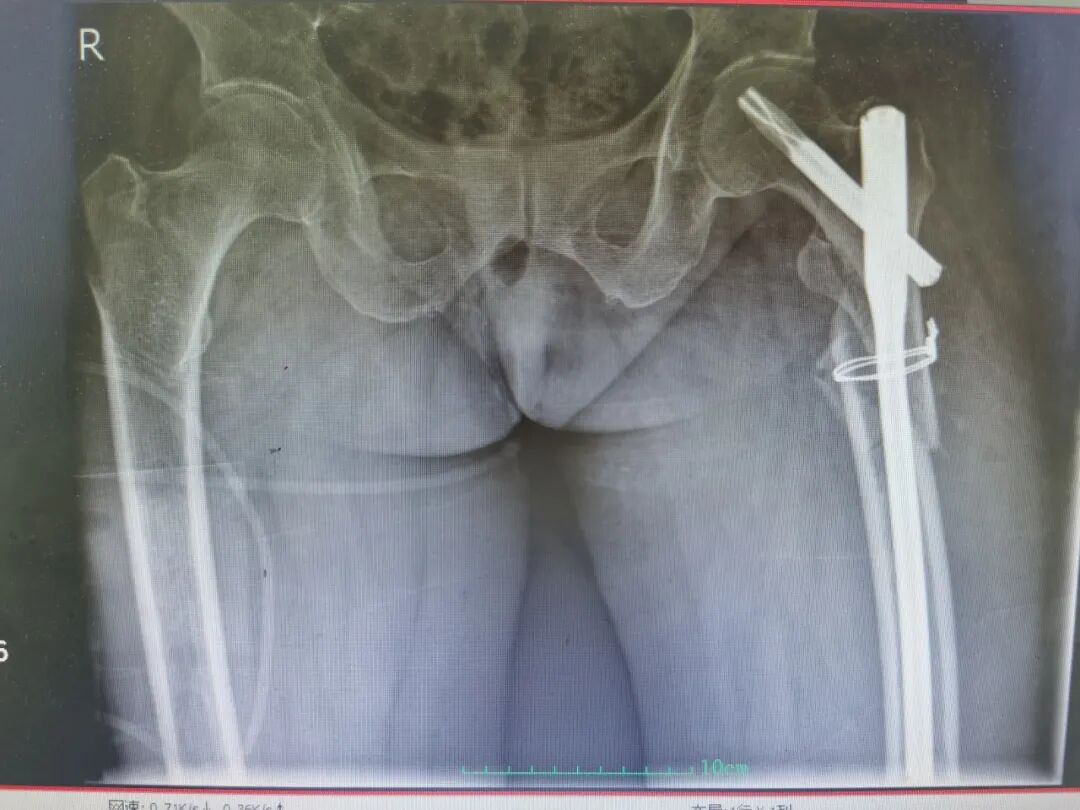

第四关,微创手术,精准麻醉 + 多科监护保驾护航。针对慕奶奶的心衰病史,麻醉科团队实施有创动脉血压监测 + 目标导向液体治疗,严格控制输液量,让麻醉过程精准、平稳;心内科专家全程在场监护,实时把控心脏情况,严防急性心衰发生。创伤与脊柱外科团队则采用股骨近端粉碎性骨折加长防旋髓内钉内固定微创技术,以最小的创伤完成骨折固定,整个手术仅用 50 分钟便顺利完成,最大程度减少了手术对高龄老人身体的刺激。

(术后影像)

在多学科团队的全程保驾护航下,慕奶奶的救治过程全程平稳:围手术期未发生急性心衰、输血相关循环超负荷等情况,血红蛋白始终保持稳定,手术切口愈合良好;术后第1天,老人便能在医护人员指导下开展床上功能锻炼,住院期间更未出现肺栓塞、感染、压疮等任何并发症,康复之路迈出了坚实的第一步。